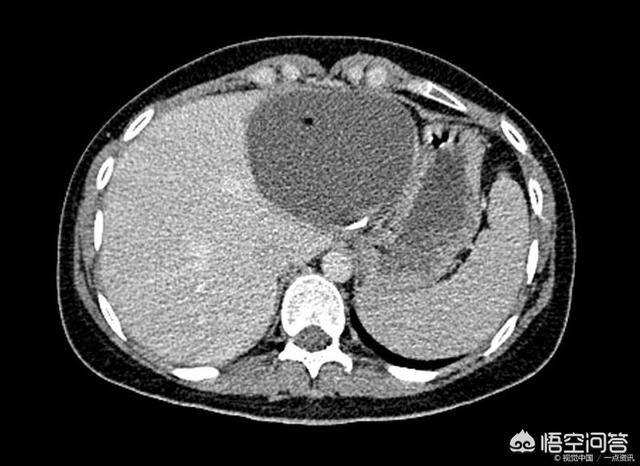

En cas de kystes hépatiques inexpliqués, il est conseillé de se rendre à l'hôpital pour une tomodensitométrie améliorée du foie et de consulter un chirurgien hépatobiliaire pour mieux comprendre la situation. Il ne faut pas être comme le patient que j'ai rencontré dans l'article précédent, qui était déprimé tous les jours jusqu'à ce qu'il connaisse la vérité.

En général, si le kyste est petit et que le patient ne présente aucun symptôme, aucun traitement n'est nécessaire et un examen régulier suffit. Si un diagnostic clair a été posé, une échographie doit être réalisée tous les six mois environ afin d'observer tout changement dans le kyste.

Dans la pratique clinique, on parle souvent de kystes hépatiques multiples comme d'un foie polykystique, et on estime qu'environ plus de 50 % des patients ont des kystes rénaux, des kystes hépatiques, et qu'un petit nombre de patients ayant des kystes hépatiques ont des lésions limitées à un lobe ou à la zone hémihépatique du foie. Les kystes hépatiques sont généralement appelés kystes hépatiques non parasitaires. La cause réelle de sa pathogenèse n'est toujours pas claire, et on observe une tendance à l'augmentation significative des pathologies dans la pratique clinique, ce qui, selon de nombreux experts, pourrait être lié à l'importance que les patients accordent aujourd'hui aux examens médicaux, ainsi qu'à la popularité des méthodes de diagnostic telles que l'échographie, la tomodensitométrie et d'autres méthodes d'imagerie.

L'examen de la fonction hépatique est généralement normal, l'examen échographique de la zone hépatique peut révéler plus d'un liquide de sécurité. La tomodensitométrie ou la scintigraphie nucléaire peuvent également vérifier la présence de kystes hépatiques multiples, en plus de déterminer que les kystes hépatiques multiples n'ont pas de lésions substantielles.